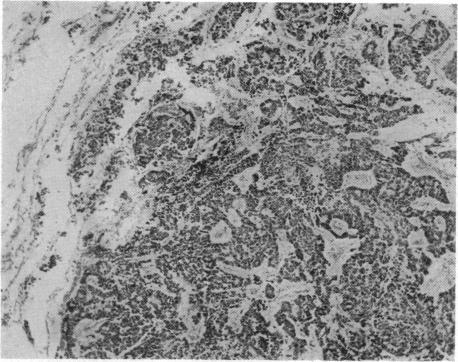

Case of Mesenteric Reticulosarcoma Associated with Gluten-sensitive Steatorrhoea.

Br Med J. 1961 Aug 19;2(5250):496-480.2. doi: 10.1136/bmj.2.5250.496.